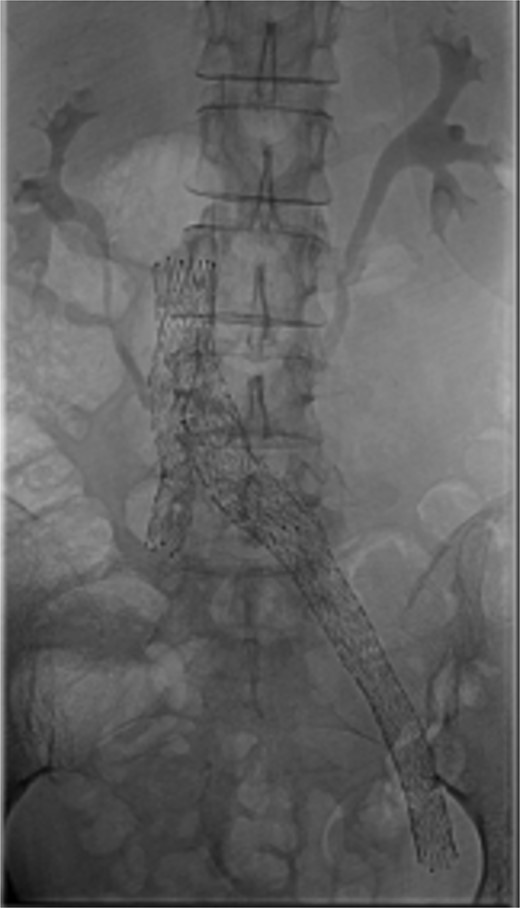

Bilateral popliteal venous access was obtained. Venography confirmed patency of the IVC, left iliac vein, and stents. Thrombolysis of the right lower limb was performed with AngioJet Zelante and 10 mg of alteplase (lower dose to minimize hematoma complications). The IVC filter was then removed to allow extension of a Venovo 12 × 80 mm stent positioned in the right iliac vein, and a Venovo 14 × 80 mm superior extension on the left. Both stents were deployed simultaneously in a ‘kissing’ configuration and post-dilatated with Mustang 12 × 100 mm balloons (Fig. 4). The completion venogram showed smooth contrast flow in both limbs with the disappearance of collateral veins.

Following thrombolysis, stenting is often required to address underlying venous stenosis [3]. Although cases of successful bilateral iliac vein stenting have been reported, the initial focus was on saving the symptomatic limb. Given the patient’s narrow caval confluence and collateral drainage of her right lower limb (Fig. 3), we did not deploy ‘kissing’ stents initially.

This case highlights valuable lessons about iliac vein stenting near the caval influence. ‘Kissing’ venous stents are safe, feasible, and should strongly be considered upfront to avoid repeat contralateral procedures. Intra-venous ultrasound (IVUS) has been recommended to guide sizing. It also helps to objectively compare the pre- and post-treatment effects [9]. In our case, IVUS was not available due to the emergency procedures being performed after hours.